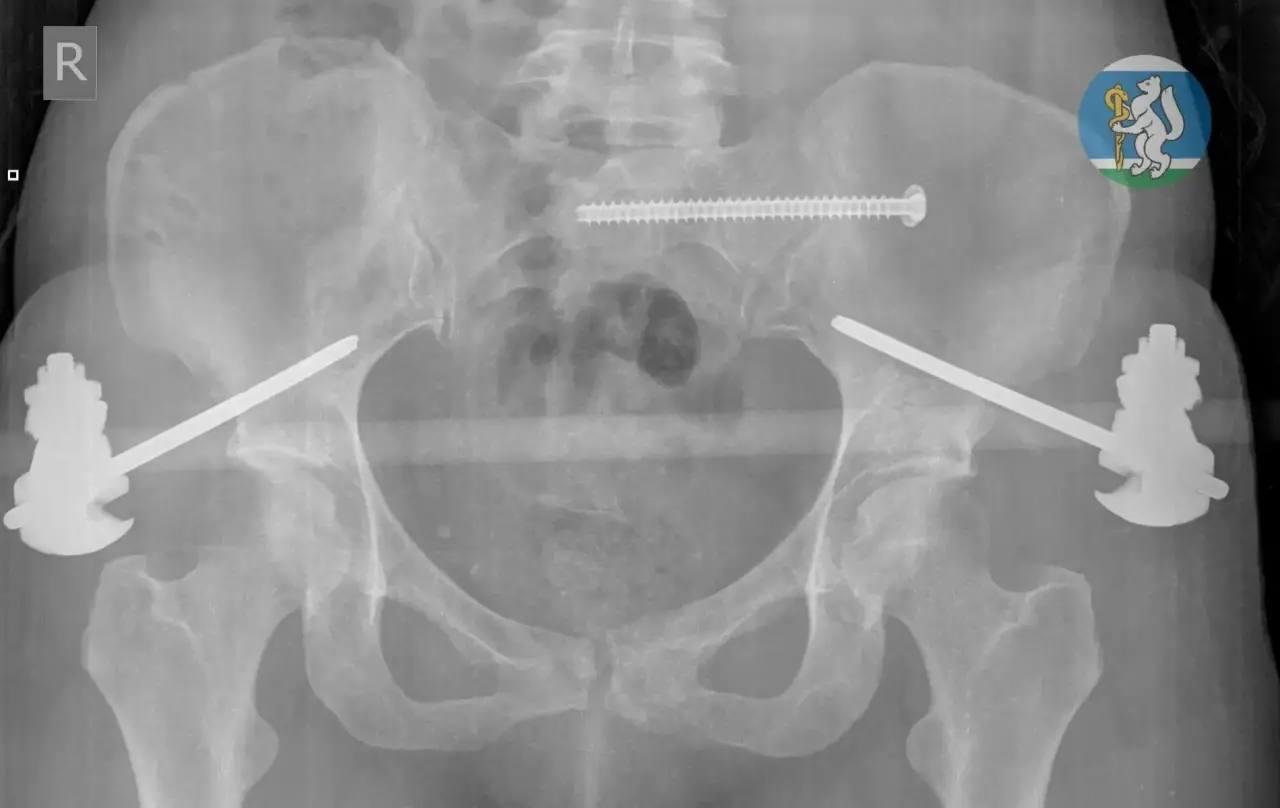

36-летняя женщина соскользнула c подоконника, когда мыла окна. Скорая забрала её с черепно-мозговой травмой, повреждением позвоночника, переломами таза и ноги.

Врачи реанимировали пациентку и провели ей несколько операций — работа шла несколько часов. Ещё месяц женщина приходила в себя в больнице. Сейчас она дома, проходит реабилитацию.